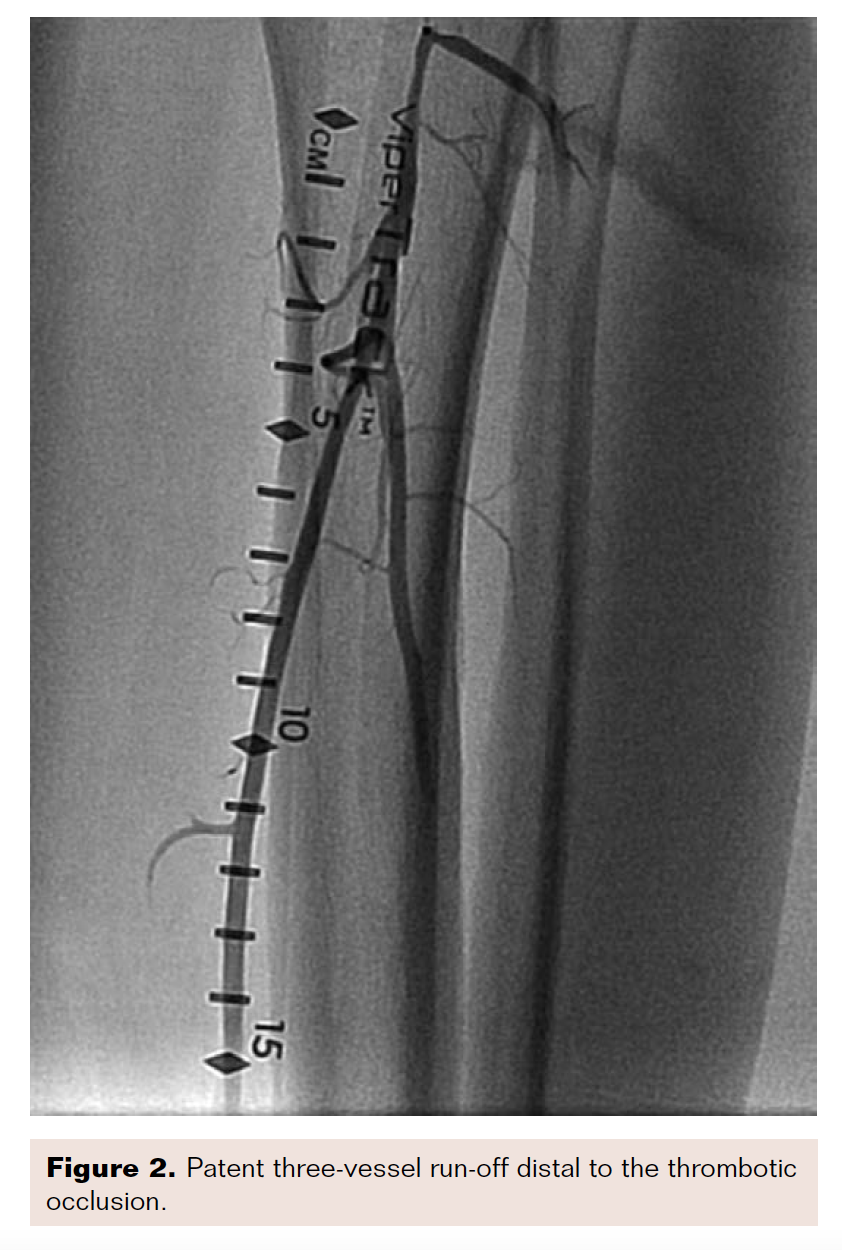

Angiogram revealed acute thrombotic occlusion of the left distal common femoral artery and SFA, with reconstitution at the tibioperoneal trunk (Figures 1-2). Initial balloon angioplasty was performed at the distal common femoral artery and proximal SFA. A 50 cm Ekos catheter was placed from the common femoral artery to the popliteal artery on the left side.